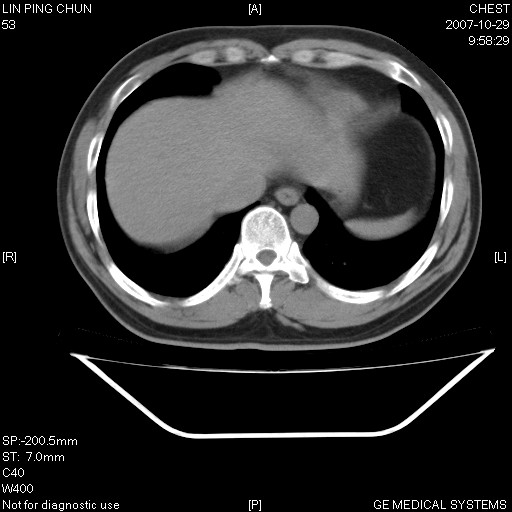

标题: CT10239:男,42Y.我自己的胸部CT扫描,今天10点突然咯血一次。

我自己胸部ct扫描,求助大家,我自己还不能给自己诊断。其他层面纵隔窗无异常。

补充:男,42y.今天10点突然咯血一次。余无异常。

左肺下叶后基底段小片结节状影,内部似见同心圆状分布条絮状影,整个病灶,质不实.局部见增粗血管影.

考虑;球形肺炎可能大.自已的身体如此重要,不进一步局部薄层及hrct?

谢谢大家!!!上传纵隔窗,请大家帮我分析。

左下肺后基底段磨玻璃样影,很多病都可以。不能吊以轻心。应该做局部增强hrct进一步检查,并严格抗炎治疗后复查或经皮活检。

左下肺后基底段小斑片泪膜玻璃样影,其内可见空泡影,边缘可见小毛刺影。建议抗炎治疗复查,肿瘤待排